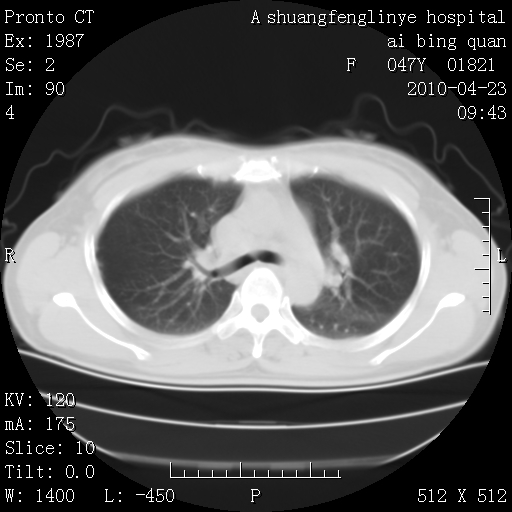

标题: CT25944:胸痛、气短、前几日高烧!肺Ca?请会诊! [打印本页]

标题: CT25944:胸痛、气短、前几日高烧!肺Ca?请会诊!

双肺多发结节,考虑转移瘤,肺癌肺转移不除外

周围型肺癌并肺转移

双肺多发结节,部分密度较高,最大结节边缘光滑。临床有“胸痛、气短、前几日高烧”病史。首选考虑:右肺感染性病变!建议积极消炎后复查!